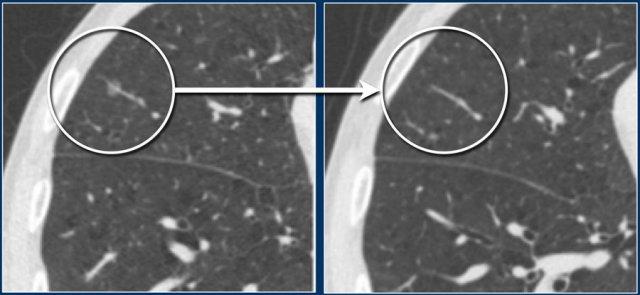

Các hình ảnh cho thấy một nốt bán đặc kính mờ thuần túy 7 mm ở thùy trên phổi phải.

Trên CT theo dõi, nốt này được xác nhận là nốt bán đặc thoáng qua.